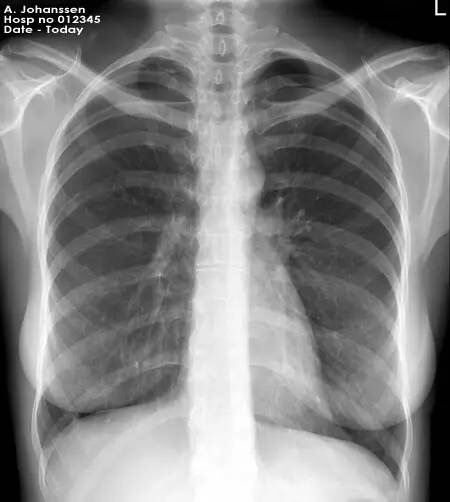

根據(jù)美國放射學會,美國婦產(chǎn)學院,美國食品藥品監(jiān)督局的臨床指導,絕大多數(shù)診斷性的放射性檢查是不會造成胎兒傷害的,如果非說有也是非常非常低的。而美國放射學會明確的說單次診斷性的x線檢查的受照射劑量根本達不到能造成胚胎或者胎兒傷害的劑量。因此單次診斷性的x線照射不能成為墮胎的理由。我一再在這里強調(diào)這個診斷性三個字,因為治療性的放射線劑量會遠遠超過診斷性放射,那是另外一回事了。

胎兒接受的x線照射如果劑量低于50毫Gy(gy是一種放射劑量單位,1gy等于100rad,50毫Gy也就是5rad,等于5000毫rad)是不會對胎兒造成健康影響的。胎兒只有受到高于100毫gy的照射才可能出現(xiàn)健康問題,而尤以孕8到25周間較為敏感。100毫gy的劑量在通常的診斷性x照射根本不會使用到,除開鋇灌腸,小腸連續(xù)成像,或者放射性治療時才有可能達到這樣高的劑量。

根據(jù)美國放射協(xié)會和婦產(chǎn)協(xié)會的數(shù)據(jù),孕婦接受單次胸部x線檢查腹中胎兒受到的照射劑量為0.02–0.07毫rad。記住,高于5000毫rad才會造成胎兒損傷。單次腹部x線平片胎兒受到的照射量為100毫rad,腎盂靜脈造影胎兒受到的照射量可能大于1rad。乳腺鉬靶檢查胎兒受到的照射量為7-20毫rad。鋇灌腸或者小腸連續(xù)成像檢查胎兒受到的照射量可以達到2-4rad。頭胸部CT檢查胎兒受到的照射量小于1rad。腹部或者腰椎CT掃描胎兒受到的照射可以達到3.5rad。

常規(guī)齒科x線檢查,頭部x線檢查,四肢x線檢查,以及胸部x線檢查,包括乳腺鉬靶檢查,或者頭胸部CT是不會對胎兒造成損傷的,兒童期癌癥的風險提高也可以忽略不計。需要做腹部檢查時請與醫(yī)生商量。所以如果孕期因為疾病的原因,或者受到創(chuàng)傷確實需要做x線檢查且沒有更佳替代,是不需要因此擔心會造成胎兒危險而拒絕檢查。你的健康不但對自己,對你的孩子也是較重要的。